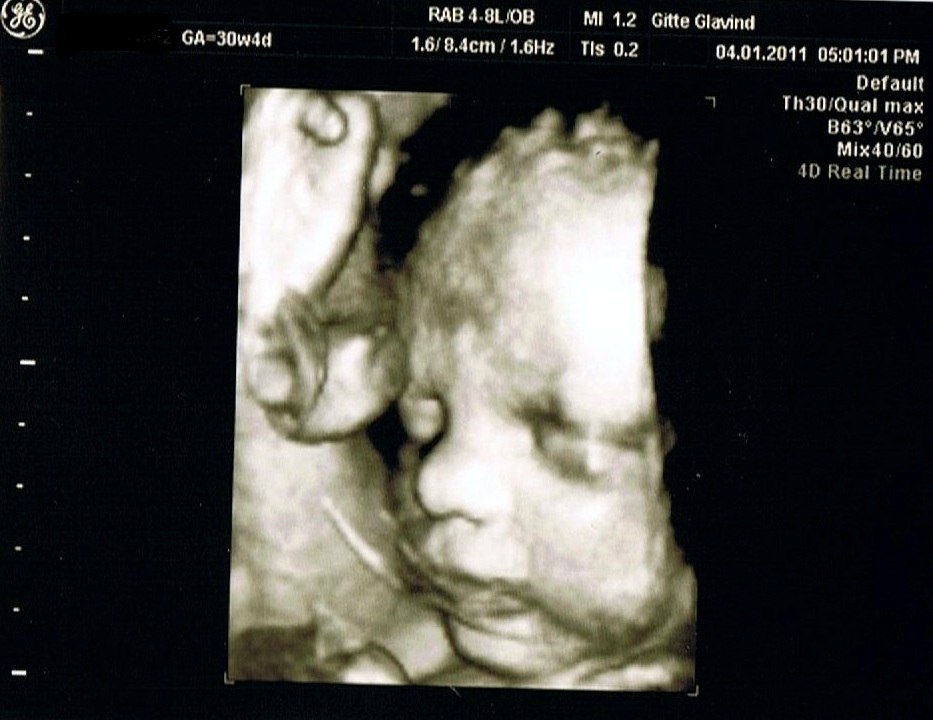

Lige 2 billeder fra skanningen, kan varmt anbefale det. Det er en utrolig oplevelse

Vedhæftede fotos (klik for at se i fuld størrelse)

Det var en utrolig dejlig oplevelse. Det bliver også sjovt at vise ham når han bliver gammel nok til at forstå det. Fik også en dvd med hjem af hele skanningen.